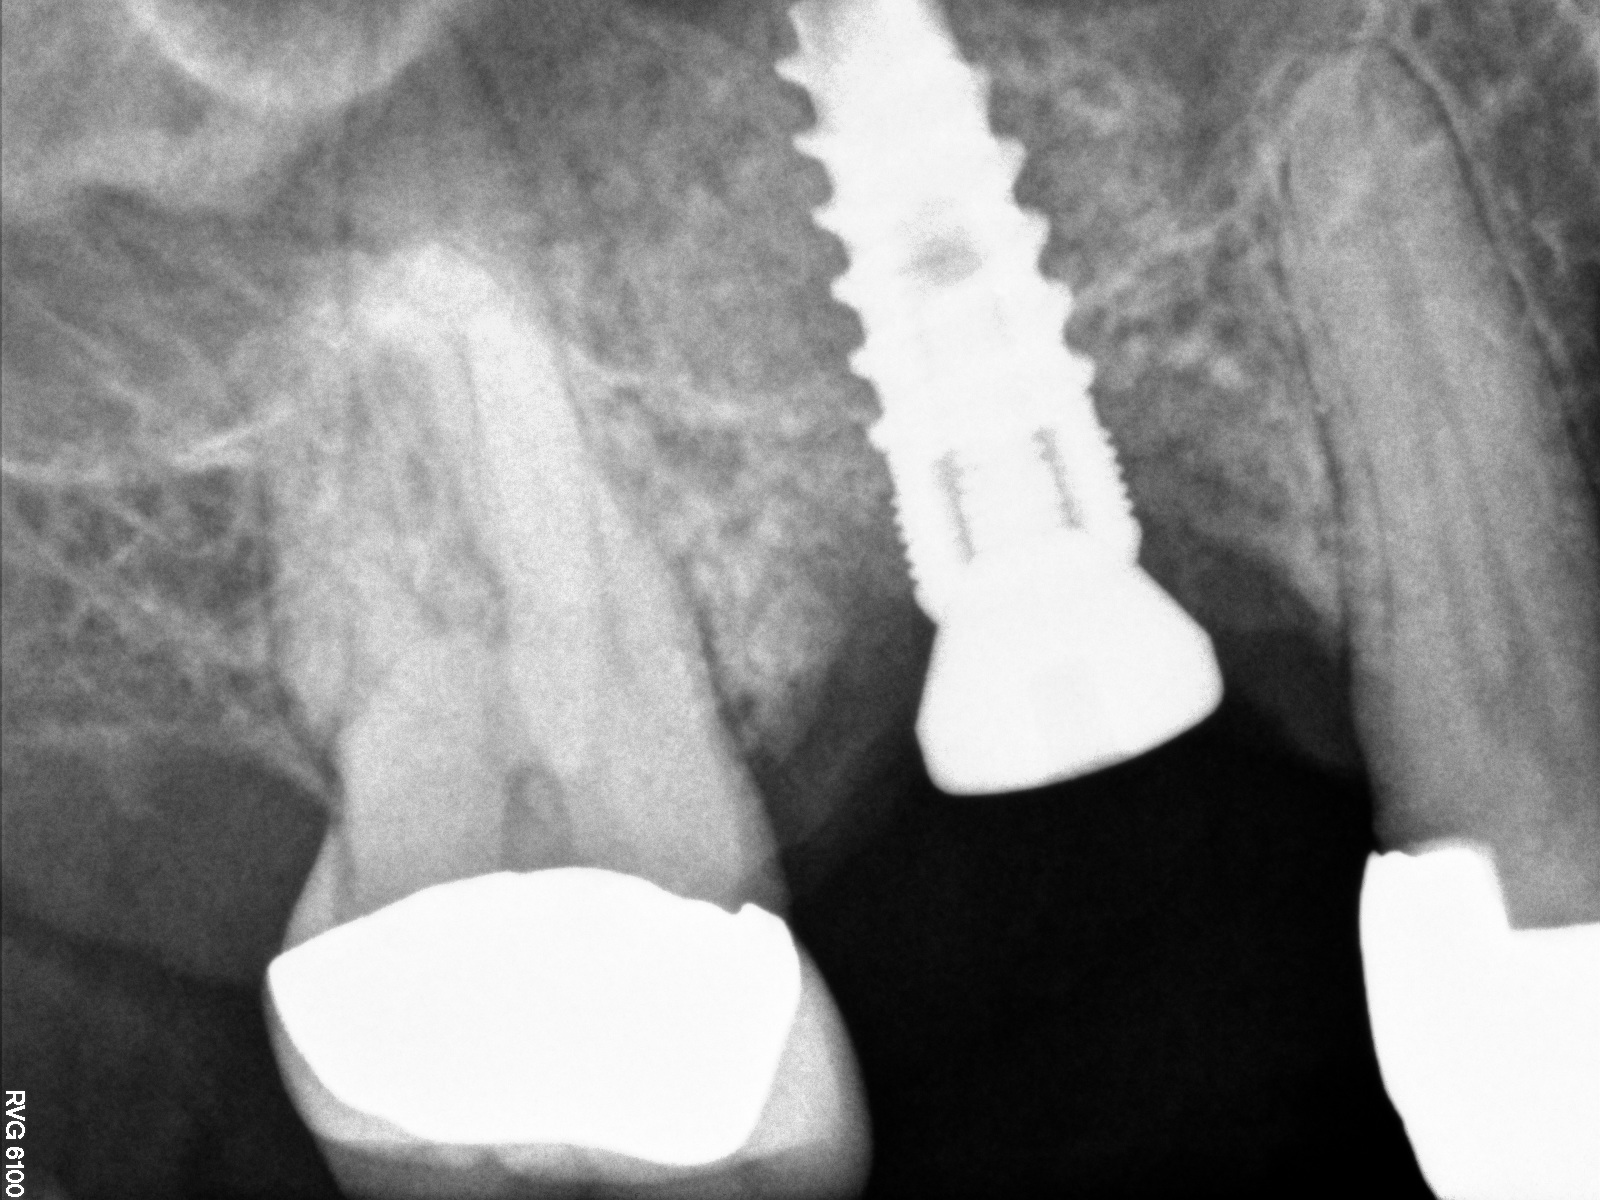

Radiograph of implant N o. 3 and sinus augmentation, day of placement. There is about 2 mm to 3 mm of native bone, and the sinus has been raised about 8 mm to 9 mm.

Fig. 10

The implant is then delivered and should be well stabilized in the bone. If there is any mobility of the implant, it can either be placed a little deeper (if there is enough native bone) or the implant can be removed and the procedure aborted, in which case it would be a two-stage procedure. This should rarely occur with the tapered designed implant, even with only 2 mm of native bone. Using a bone-level platform-shifting implant (or a tissue-level designed implant) is critical, as the hard and soft tissue will establish a biologic width. If an external hex type of implant is used and the shoulder is placed at the bone level, an expected bone loss of 1.5 mm to 2 mm will occur.24 Figure 10 shows proper bone-level implant depth placement with a platform-shifting design. In this case, a 3-mm healing abutment was placed at the time of surgery to avoid a secondary uncovering surgery, but an implant-level healing abutment could have been placed instead. As can be seen, there was only about 2 mm to 3 mm of native bone height. The membrane was raised about 8 mm to 9 mm. Comparing the radiograph on the day of surgery (Figure 10) to the 6-month postoperative radiograph (Figure 11) shows no loss of native bone, as well as the positive change in appearance of the grafted bone. The 3.5-month CBCT scan (Figure 12) shows good healing of the bone with no coronal bone loss. With minimal native bone present, as in this case, the use of a non-platform-shifting or non-tissue-level implant design could be problematic. After 1.5 mm to 2 mm of crestal bone loss, an external hex designed implant could develop instability with possible implant failure. If a non-tapered implant is used and bone loss occurs during healing, migration of the implant into the sinus could potentially occur. The surgeon can use either a healing abutment or implant-level closure screw over the implant shoulder. With patients who tend to use their tongues to explore or play with the area, or if the area is under a removable partial denture, a closure screw is recommended.